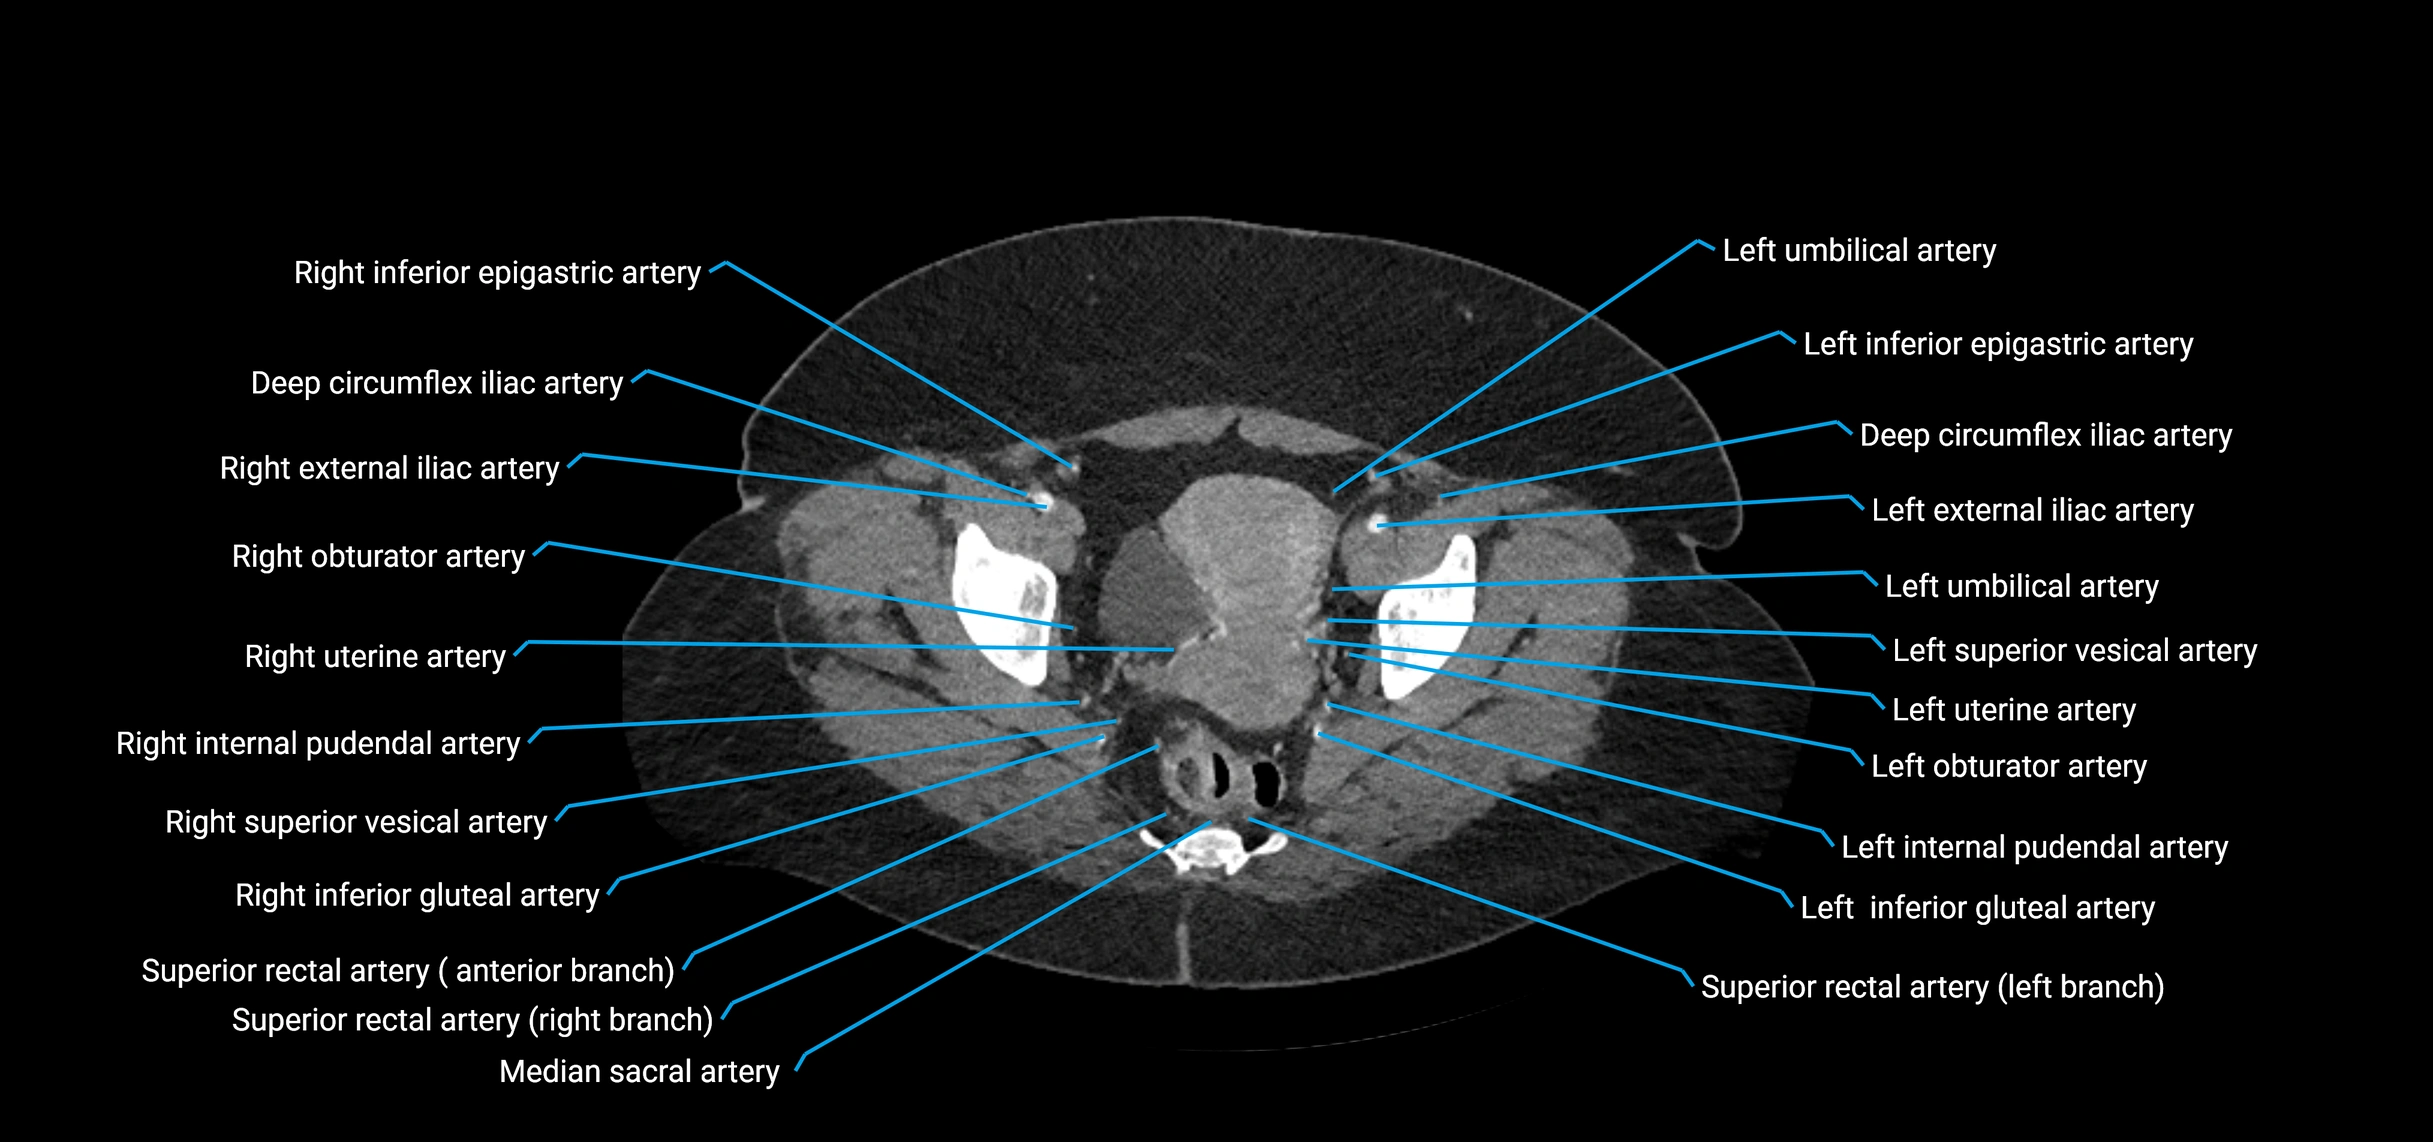

CT images

image

Contrast-enhanced CT (CTA):

• Gold standard for abdominal aortic imaging

• Provides excellent detail of lumen, wall, aneurysm, thrombus, and branch vessels

• Multiplanar and 3D reconstructions help in aneurysm measurement, stent graft planning, and dissection evaluation